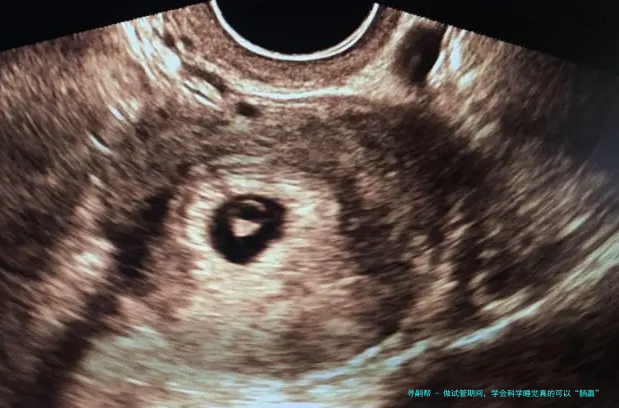

二、胚胎移植后。从医院抵家休息,要严密按医嘱躺床休憩满48小时,因为这个时间是囊胚移植后游离寻找俱佳着床位置的时间段,充分在床上休憩的要求是准妈妈除了正常的吃饭和如厕外,都须要十足卧床休息,在床上姿势可以是平卧、侧躺或斜卧,注意斜卧的姿势要小于四十五度。如厕时要抉择坐便的方式,避免深蹲、身体动作幅度大而影响到囊胚的游离,防备异位妊娠或滑胎的出现。48小时之后,就能正常生活和事业了,防止久卧对身体血液、心理压力、睡眠、身体代谢和排毒素等方面的影响,反而不利于胚胎的着床和胎儿健康发育。尚有少许,便是维系轻快愉悦的心态,相信并对试管婴儿抱有等待,如此结果就可以正向发展了。